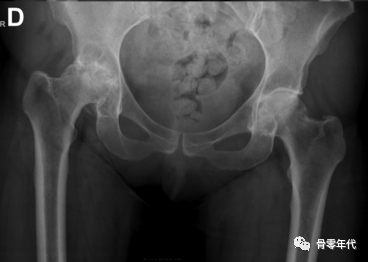

用于目标肢体延长的关节炎严重程度分级。(A)关节间隙轻度变窄的目标是延长2-3 mm。(B)完全缩小关节间隙的目标是加长4-5mm。(C)股骨头扁平或髋臼骨质侵蚀可延长5~6mm。(D)股骨头和髋臼侵蚀的目标是延长6mm或更长。